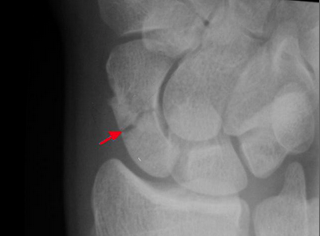

The above xrays show a scaphoid waist fracture (indicated by the red arrow) before fixation and showing solid union after screw fixation.